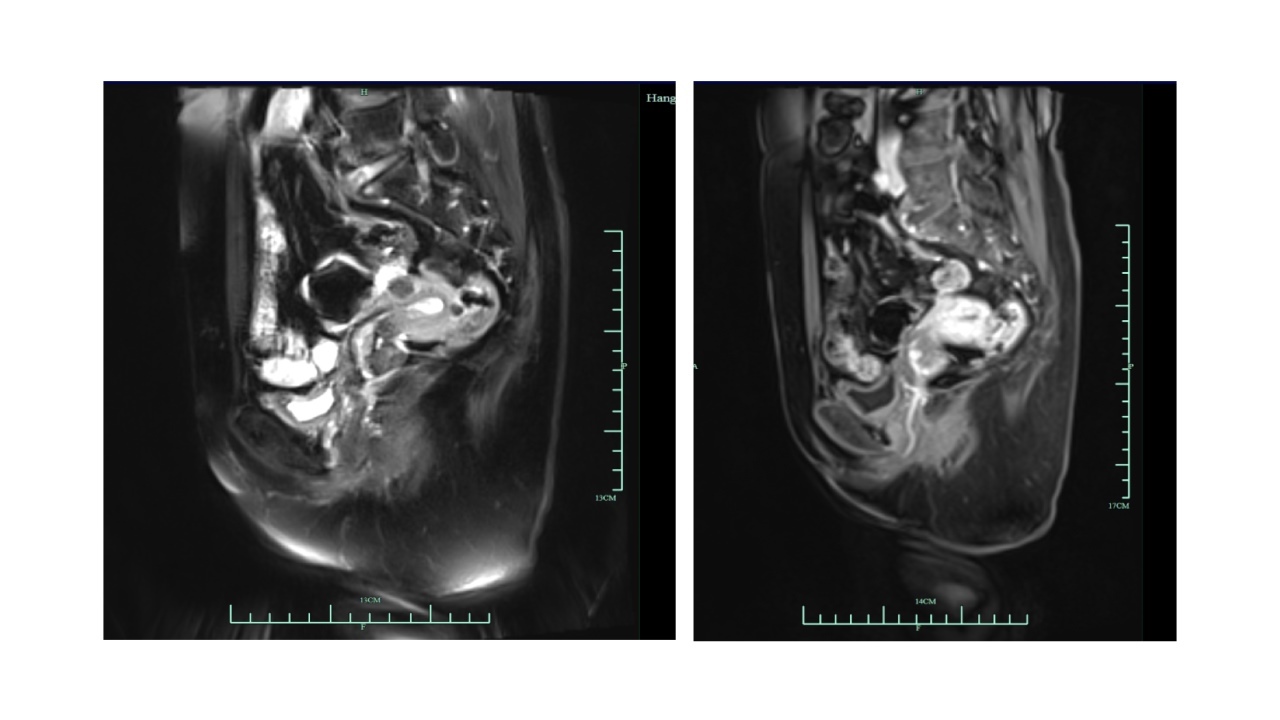

(2022-9-22本院)盆腔磁共振:宫颈后壁软组织信号灶(大小15*12mm),宫颈癌考虑。子宫肌瘤考虑。宫腔少量积液。